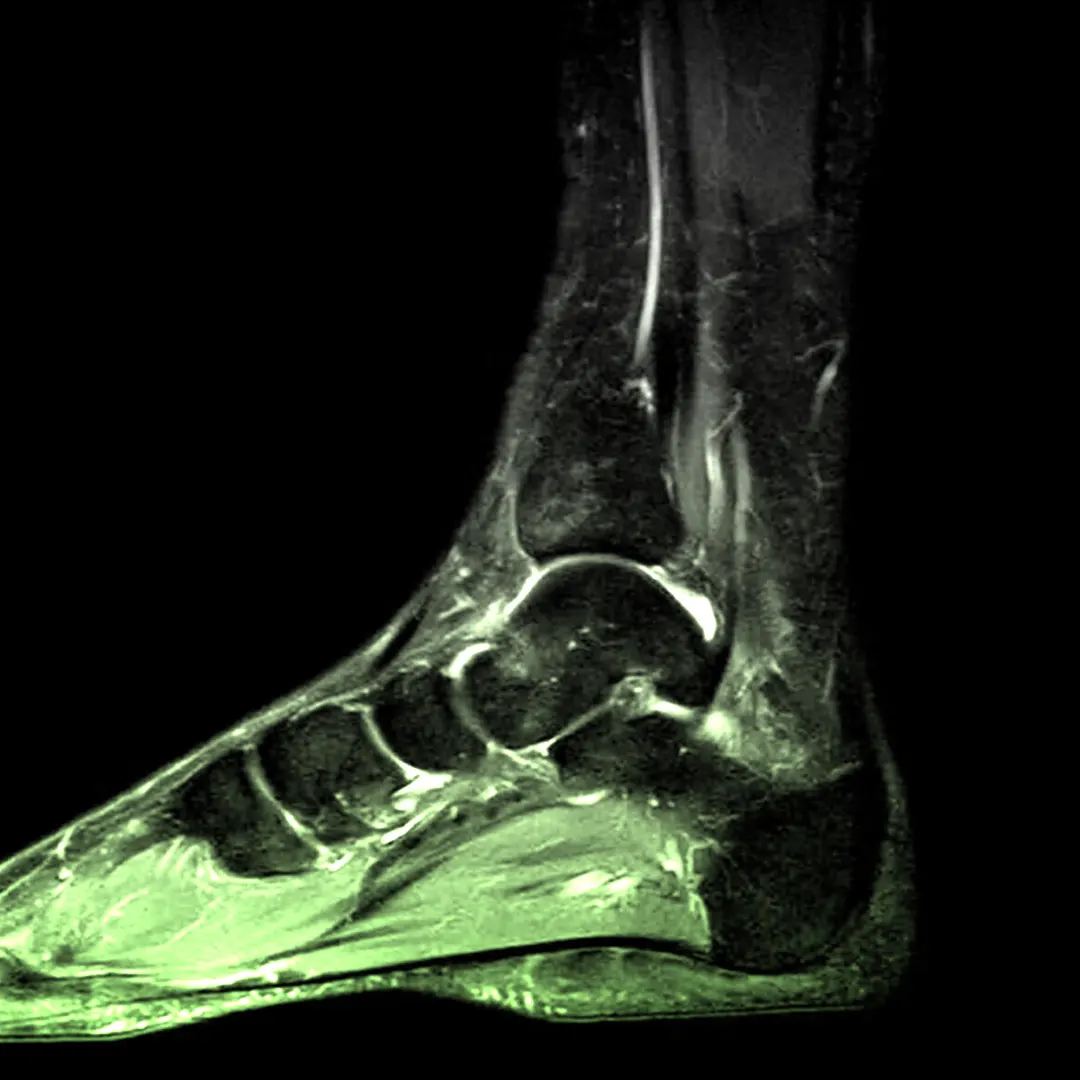

Анатомічна будова гомілки

Гомілка складається з двох кісток: великогомілкової та малогомілкової. Перша — масивна й бере на себе основне навантаження. Друга — тонша, але важлива для стабільності. Якщо порівняти їх, великогомілкова кістка більше схожа на міцну колону, а малогомілкова — на опору, яка допомагає зберігати рівновагу. Разом вони формують основу для колінного й гомілково-стопного суглобів.

Фасції та зв’язки розділяють гомілку на відділи, створюючи «комірки» для м’язів і судин. Завдяки цьому все працює злагоджено, а рухи залишаються точними. Уявіть, як легко було б травмуватись, якби цього природного поділу не існувало.